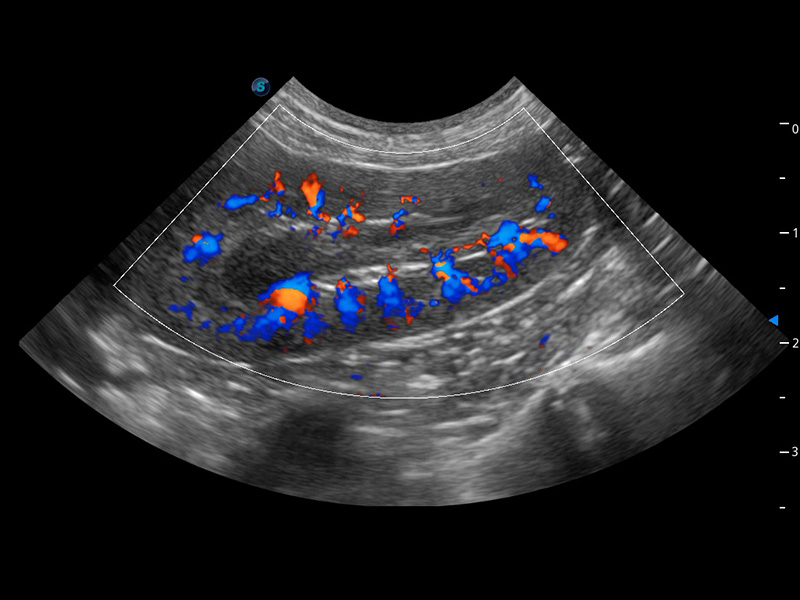

(犬)肾脏血流

PDI 能量多普勒血流

提供高灵敏度和空间分辦率的血流图像,获得更加真实和丰富的诊断信息。

SR Flow 高分辨率血流成像

能够清晰显示细小、低速血流图像,获取传统彩色多普勒技术难以得到的细节和信息。